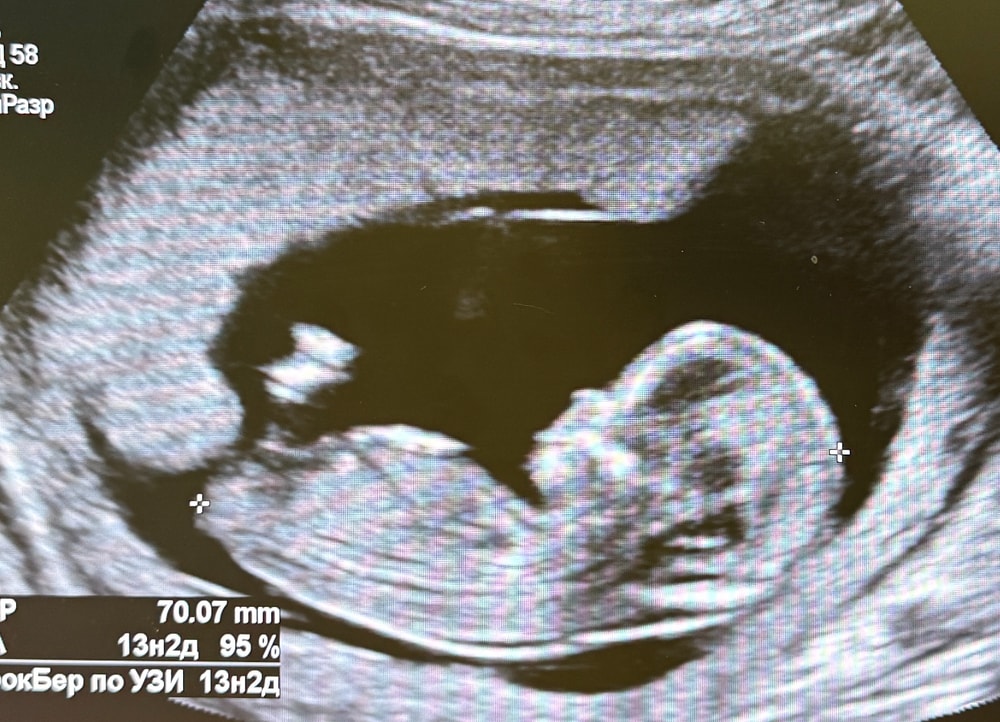

Узи 13 неделя

Здесь 12+6 🩵 Изображение